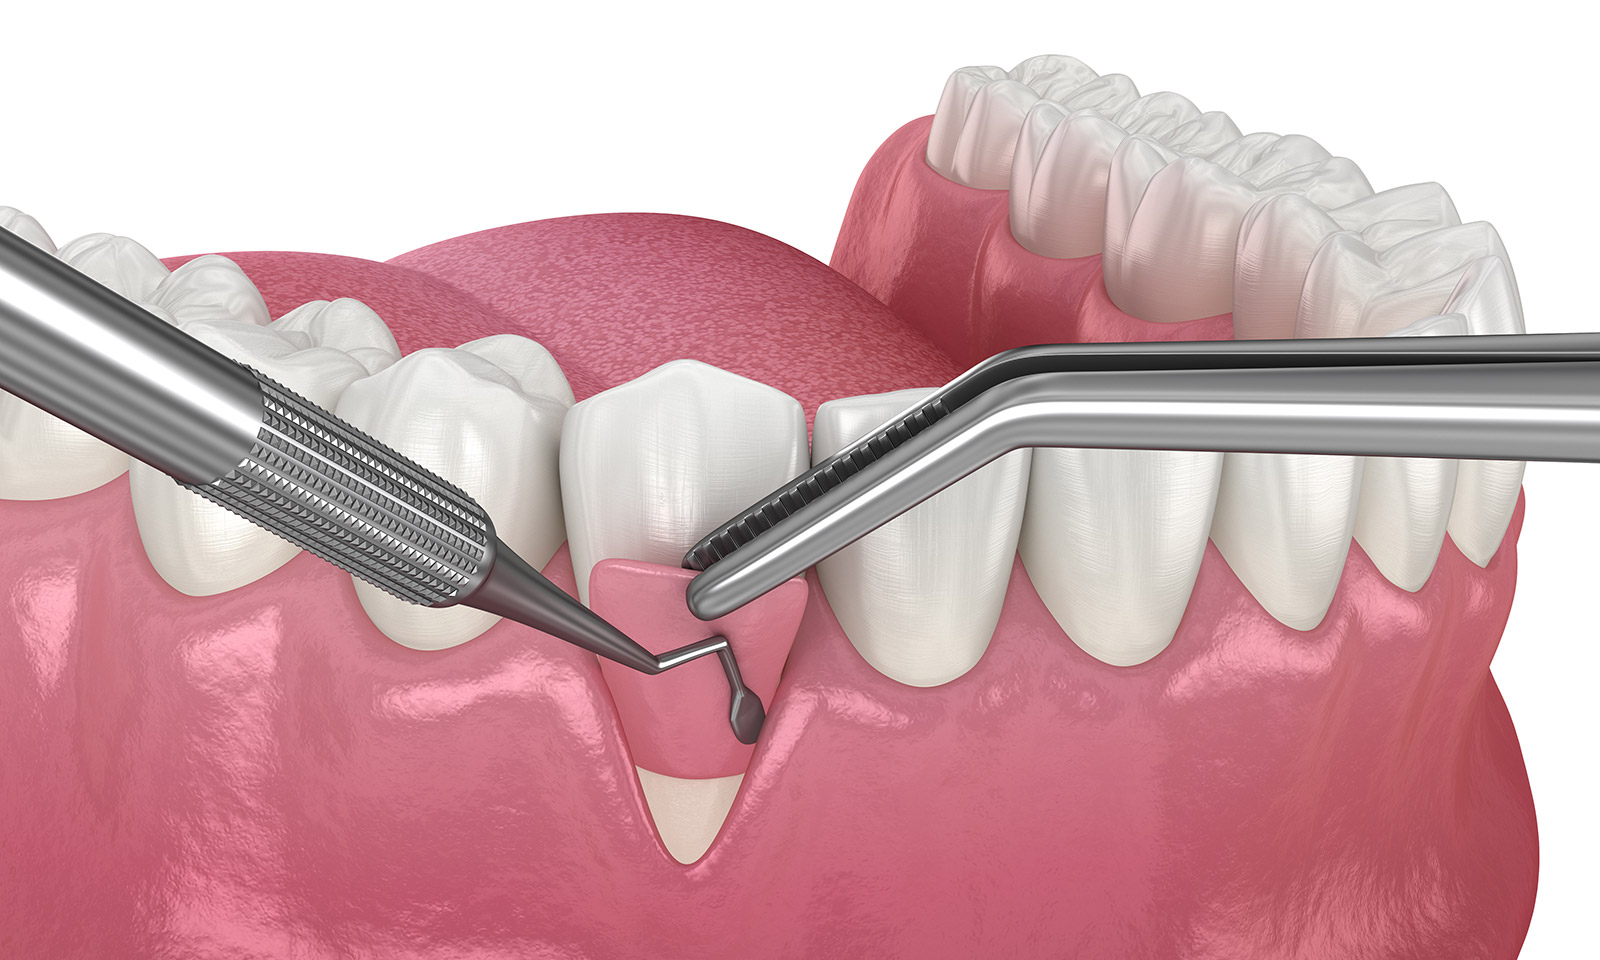

歯周病が進行すると歯周ポケットが深くなってしまい、通常の処置では歯石を取り除くことが難しくなります。この状態のまま放置してしまうと歯周病はさらに悪化し、歯が抜けるのも時間の問題となります。

この状態に対して有用なのが「歯周外科治療」です。歯肉を外科的に切開するなどして、深い部分に付着した歯石を取り除いていきます。

FOP法

「FOP法」は、歯茎を部分的に切開して歯石を取り除き縫合する治療方法です。切開することで、歯周ポケットの奥に溜まった歯石を取り除くことができます。奥底に溜まった歯石や汚れを取り除くことで、歯茎の炎症を回復させるだけでなく、歯周ポケットを徐々に浅くすることもできます。